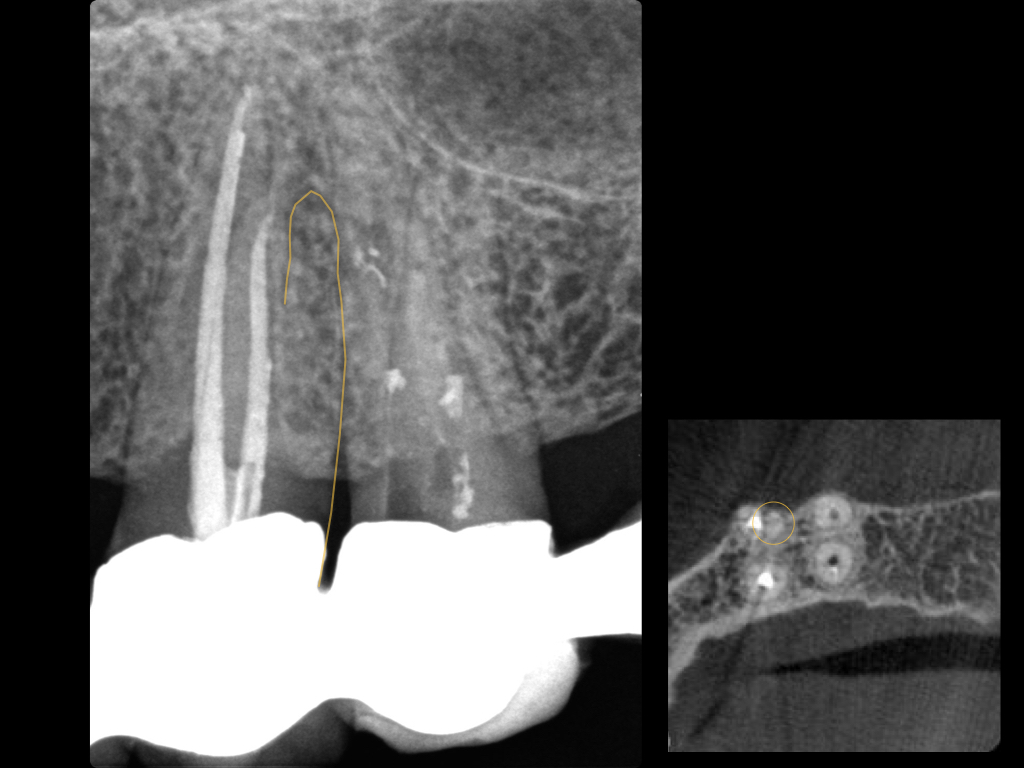

Es ist zu sehen … (2)